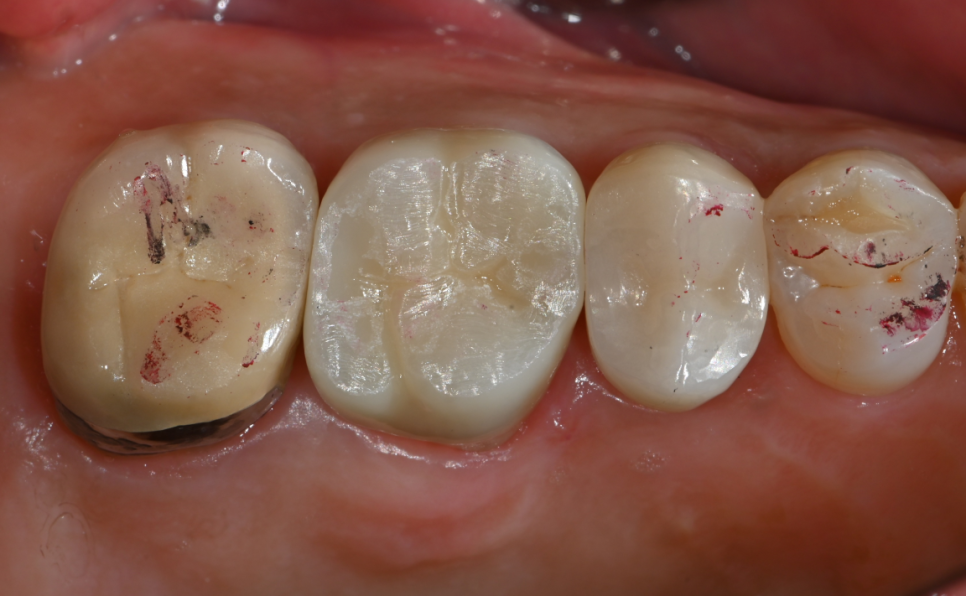

오래가는 크라운 치료를 위해 보철과 원장님께서 치아를 다듬은 모습!

신경치료를 잘 마무리 하고

치아를 보호하기 위해

지르코니아 크라운으로 씌워드렸습니다

지르코니아는 자연치아와 비슷한 색깔과 튼튼한 재료로

심미성과 기능성을 모두 갖춘 크라운 재료입니다

완성 후 교합검사까지 완료한 지르코니아 크라운

치아를 최대한 보존하면서도

좋은 크라운 치료가 되기 위해서

보철과 전문의 원장님이 치아 형태를 다듬고,

지르코니아 크라운으로 치료를 마무리 했습니다👍

환자분께서 치료 후 식사하실 수 있다고하셔서

저희도 매우 기뻤습니다😄